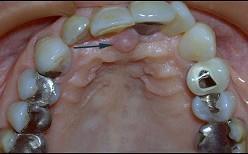

问题 切牙乳突是排列上中切牙的解剖标志、是因为 ( )

选项 A.切牙乳突的位置变化较小 B.切牙乳突位于上颌腭中缝的前端 C.切牙乳突与上颌中切牙之间有较稳定的关系 D.两个上中切牙的交界线应以切牙乳实为准 E.切牙乳突下方为切牙孔、排牙时要防止此处压迫

答案 C